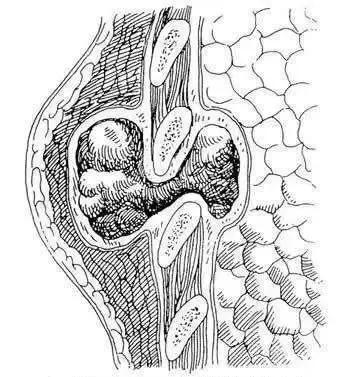

脊柱结核病人常有结核病史,同时多有午后低热、消瘦、贫血等伴随症状,从感染到出现相应临床表现一般需11.2 个月。部分区域疼痛、按压痛、肌肉僵直、病灶周围脓肿、脊柱畸形等,是脊柱结核的典型临床表现。

3、治疗:多数脊柱结核可通过非手术治疗获得痊愈,手术治疗是脊柱结核治疗的终极手段,其目的是清除病灶,解除脊髓、神经压迫,矫正后凸畸形和重建脊柱稳定性。目前脊柱结核手术入路主要有前路、后路、前后联合入路及微创术式。